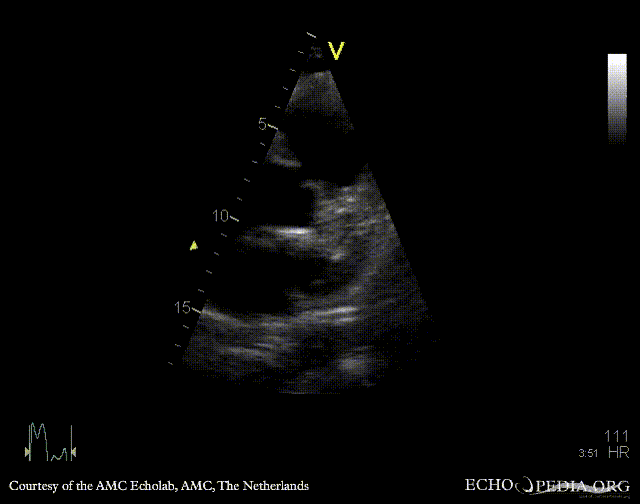

| Courtesy of: AMC Echolab, AMC, The Netherlands | |

| Suprasternal view | Suprasternal view |